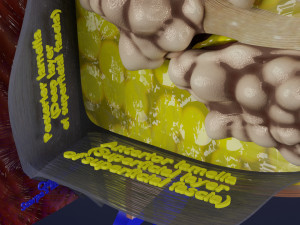

Breast anatomy histology detailed labelled precise to scale model 3D Модель

This is a 1:1 scaled model of right breast cut opened in sagittal plane to reveal its internal antomy and histology (schematic). The deeper parts and fascial layers are also depicted to give a very detailed approach to the model. The full layers starting from skin, nipple areola, till intercodtal muscles and ribs are also depicted.

breast mammary gland female chest wall anatomy human medical science reproductive genitalia muscle fascia milk nipple areola subcutaneous fatДо даного товару немає коментарів.